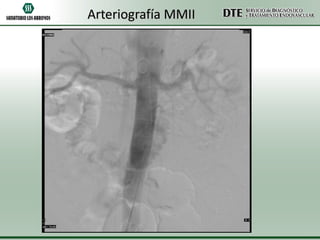

Arteriografía MMII

Arteriografia MMII

•Conclusiones:

•Oclusión completa de arteria poplítea izquierda

•Oclusión de arteria tibial posterior derecha

•Conclusiones: •Oclusión completa dearteria poplítea izquierda •Oclusión de arteria tibial posterior derecha